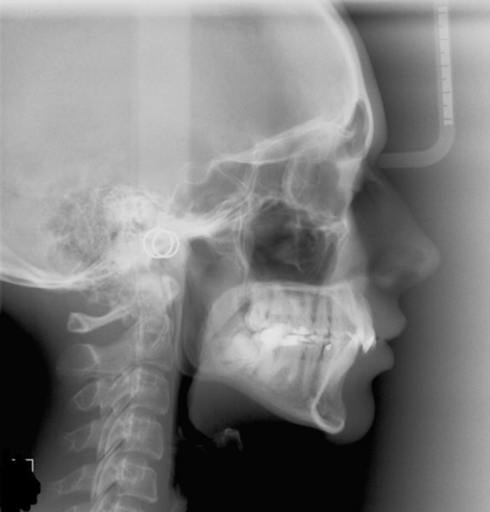

I\'m 28 and have an underbite that I\'d like corrected and am looking to the find the most low profile and least life intruding method of doing so. I had braces in high school and, originally, the plan was to have Orthognathic Surgery to correct it. However, we just didn\'t have the money to go through with it. Also, the procedure to surgically fix the bite scares me, frankly, and I\'d like to avoid it if possible. Now, I\'ve heard that there are rare cases in which an adult\'s underbite has been fixed via headgear. Would it possible to have linguistic braces with headgear to fix an adult underbite?